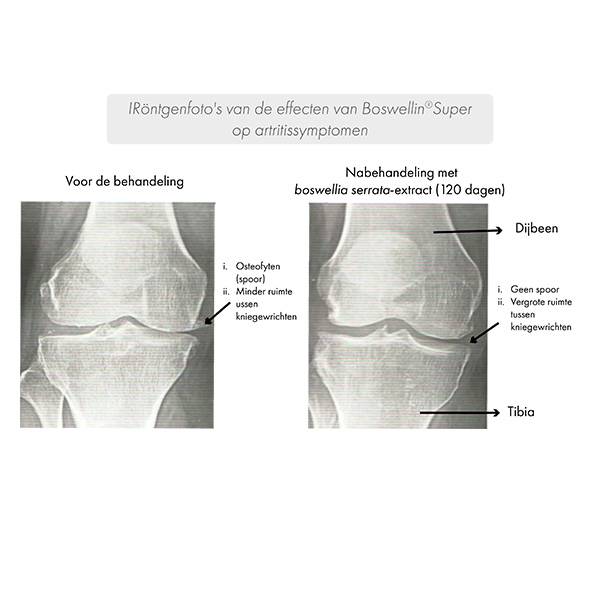

Tegelijkertijd werd verbetering van de symptomen aangetoond op röntgenfoto's.

Na 120 dagen werd een verbetering van de inter-articulaire ruimte en een afname van osteocyten aangetoond.